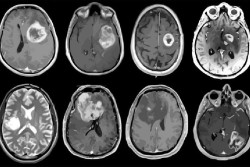

Los investigadores han desarrollado el mayor y más completo mapa molecular hasta la fecha del subtipo de cáncer de pulmón carcinoma de células escamosas de pulmón. Su trabajo reúne datos proteómicos, transcriptómicos y genómicos en una visión proteogenómica detallada que ha revelado posibles nuevas dianas farmacológicas, vías de regulación inmunitaria que podrían ayudar al cáncer a evadir las inmunoterapias e incluso un nuevo subtipo molecular, según publican en la revista `Cell`.